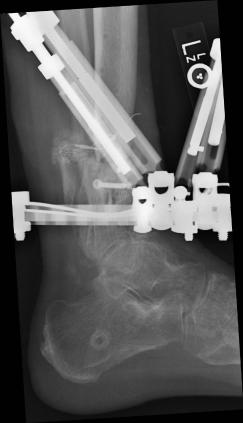

Postoperative (13th) images of left ankle

The image(s) displayed here were created following Liam's 13th surgery which was performed by Dr. Saunders. After a few hiccups getting

the surgery scheduled, Liam spent most of the September 13th afternoon in his 13th surgery. ;-) The surgery lasted about 5 hours and according

to the doctor, it was a good surgery. The 1st photo shows the new frame bracing that holds Liam's ankle together. The next series of photos show

various angles of the ankle and the rods that go from the frame into and through the left ankle. There was some concern that the swelling would

burst and allow for infection. Looks like we are now past that concern. Liam is still on antibiotics to ward of potential infection. The flesh

images show how the skin reacts to having the leg adjusted by the brace. The doctor has had to cut the skin to allow the rods to move freely.